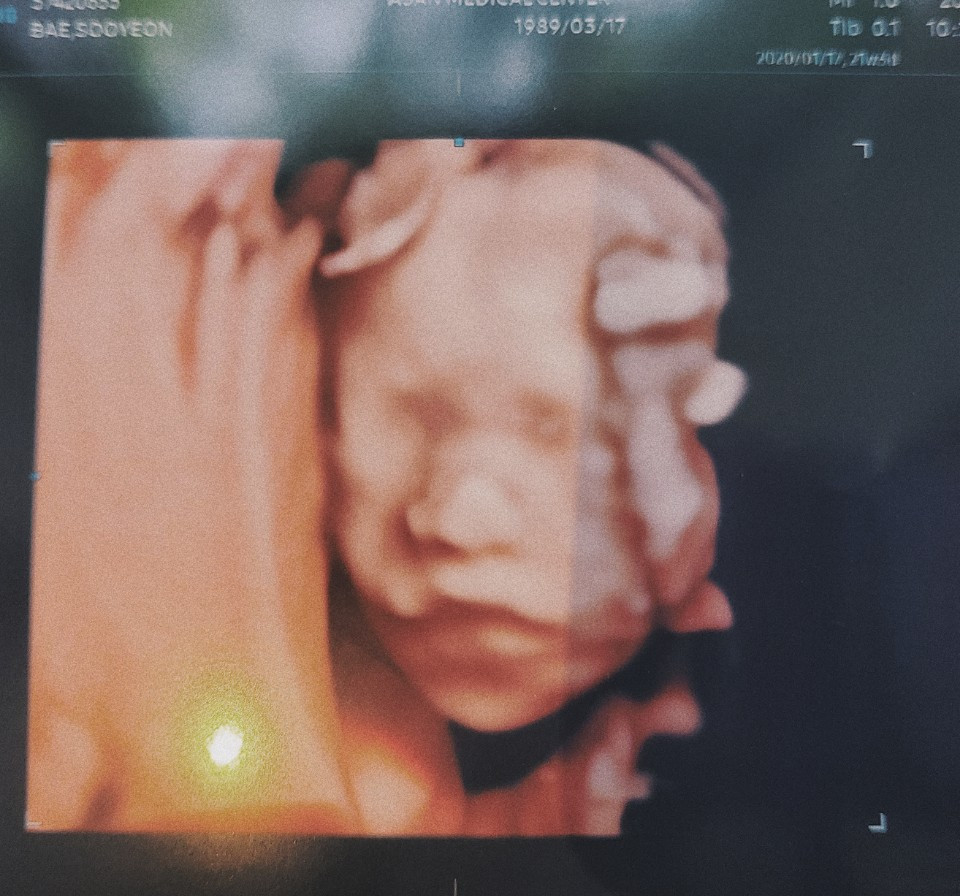

며칠 전 병원을 들려 정밀 초음파를 통해서 까꿍이를 정말 자세하게 들여다봤다. 주차 보다 조금 크다는 소리에 우리 까꿍이가 잘 먹고 있구나라고 안심했다. 참 엄마라는 타이틀이 아직도 낯설고 어색하기만 하다. 그렇지만 뱃속에서 조금씩 움직이는 아가를 느낄 때면 한 번도 느껴 보소 한 감정들이 느껴질 때가 있다.

22차 까꿍이